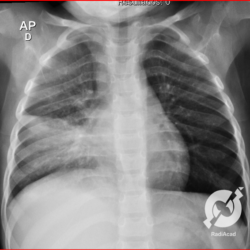

E o nome dado a esta alteração radiográfica que corresponde à substituição do ar alveolar por líquido é a consolidação alveolar.

Uma consolidação alveolar é, por definição, uma opacidade (imagem densa, branquinha) homogênea ou às vezes heterogênea (pela presença de calcificações ou cavidades), de limites mal definidos, exceto quando toca a pleura da parede ou das cissuras pulmonares. É um termo usado tanto em radiografia, como em tomografia computadorizada. Na tomografia, um outro termo é usado: vidro fosco, que é uma opacidade (branquinha mas não tanto como a consolidação), que borra o pulmão mas deixa ver os vasos de permeio (igual bigode de adolescente: dá pra ver todo o fundo).

Nós vamos mostrar aqui um pequeno apanhado de pneumonias de variados agentes, em diversos segmentos e lobos pulmonares, com extensões variadas. O objetivo é identificar o padrão radiológico de consolidação alveolar e não determinar o agente infeccioso, isso vai ser assunto para mais adiante. Aliás já antecipo que é fundamental saber localizar a lesão, porque alguns destes bichos gostam de determinados segmentos, alguns tumores também têm as suas preferências, então localização é fundamental. Se localização não fosse importante, um apartamento na beira do mar sairia o mesmo preço de um apartamento de frente pra BR-101, concordam?

Seguem alguns dos nossos casos de pneumonia para vocês treinarem os olhos e não se apavorarem nos plantões.